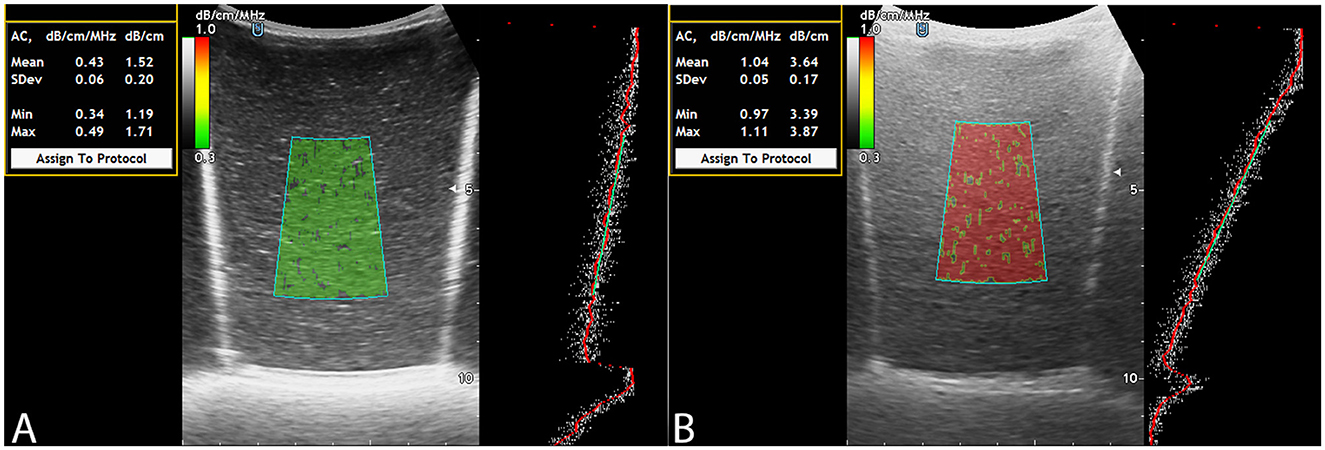

To evaluate the visual and quantitative expression of fat content using ACM, color mapping patterns in the LFPs were analyzed. The color of the ROI in ACM mode on the Soneus 7 system changed progressively with increasing fat concentration, closely resembling the appearance of hepatic parenchyma in clinical imaging. Phantoms with minimal fat exhibited low attenuation and were characterized by a uniform green hue, whereas higher fat concentrations resulted in progressively greater attenuation and a shift in the color map toward yellow and red shades (Figure 2).

Figure 2

ACM: fat-free LFP (A), LFP filled with fat solution (B).